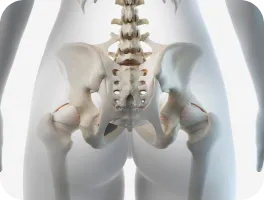

골반전방경사(오리엉덩이)

또한 골반과 대퇴골 경골의 회전과 틀어짐, 발 아치의 높이와 발의 비대칭까지 파악하여 원인을 교정합니다.